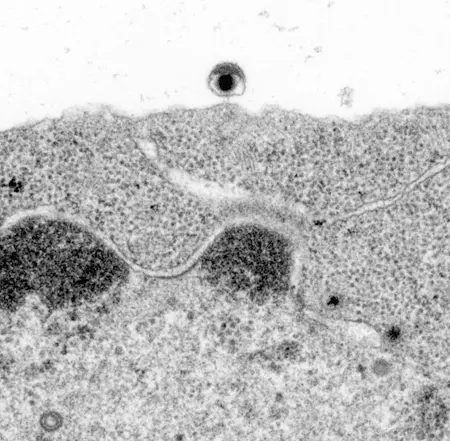

Epstein-Barr Virus beim Verlassen einer Zelle (elektronenmikroskopische Aufnahme)

Epstein-Barr Viren (EBV), Mitglieder der Familie der Herpesviren, sind bei uns in erster Linie als Erreger des Pfeifferschen Drüsenfiebers – der so genannten Kuss-Krankheit bekannt. In anderen Teilen der Welt begünstigt das Virus dagegen Krebserkrankungen; in Zentralafrika das Burkitt-Lymphom, im asiatischen Raum dagegen verschiedene Tumoren des Nasen-Rachenraums. Schätzungen gehen davon aus, dass etwa zwei Prozent aller Krebsfälle weltweit auf das Konto von EBV gehen.